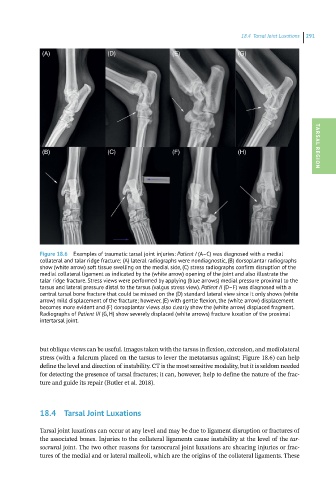

Figure 18.6 Examples of traumatic tarsal joint injuries: Patient I (A–C) was diagnosed with a medial

collateral and talar ridge fracture; (A) lateral radiographs were nondiagnostic, (B) dorsoplantar radiographs

show (white arrow) soft tissue swelling on the medial side, (C) stress radiographs confirm disruption of the

medial collateral ligament as indicated by the (white arrow) opening of the joint and also illustrate the

talar ridge fracture. Stress views were performed by applying (blue arrows) medial pressure proximal to the

tarsus and lateral pressure distal to the tarsus (valgus stress view). Patient II (D–F) was diagnosed with a

central tarsal bone fracture that could be missed on the (D) standard lateral view since it only shows (white

arrow) mild displacement of the fracture; however, (E) with gentle flexion, the (white arrow) displacement

becomes more evident and (F) dorsoplantar views also clearly show the (white arrow) displaced fragment.

Radiographs of Patient III (G, H) show severely displaced (white arrows) fracture luxation of the proximal

intertarsal joint.

but oblique views can be useful. Images taken with the tarsus in flexion, extension, and mediolateral

stress (with a fulcrum placed on the tarsus to lever the metatarsus against; Figure 18.6) can help

define the level and direction of instability. CT is the most sensitive modality, but it is seldom needed

for detecting the presence of tarsal fractures; it can, however, help to define the nature of the frac-

ture and guide its repair (Butler et al. 2018).